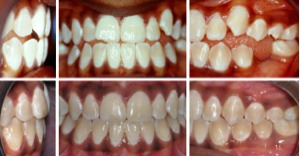

Fall 4: Kopfbiss / Unterkiefervorlage mit seitlich offenem Biss

Therapie: Festsitzende Spange